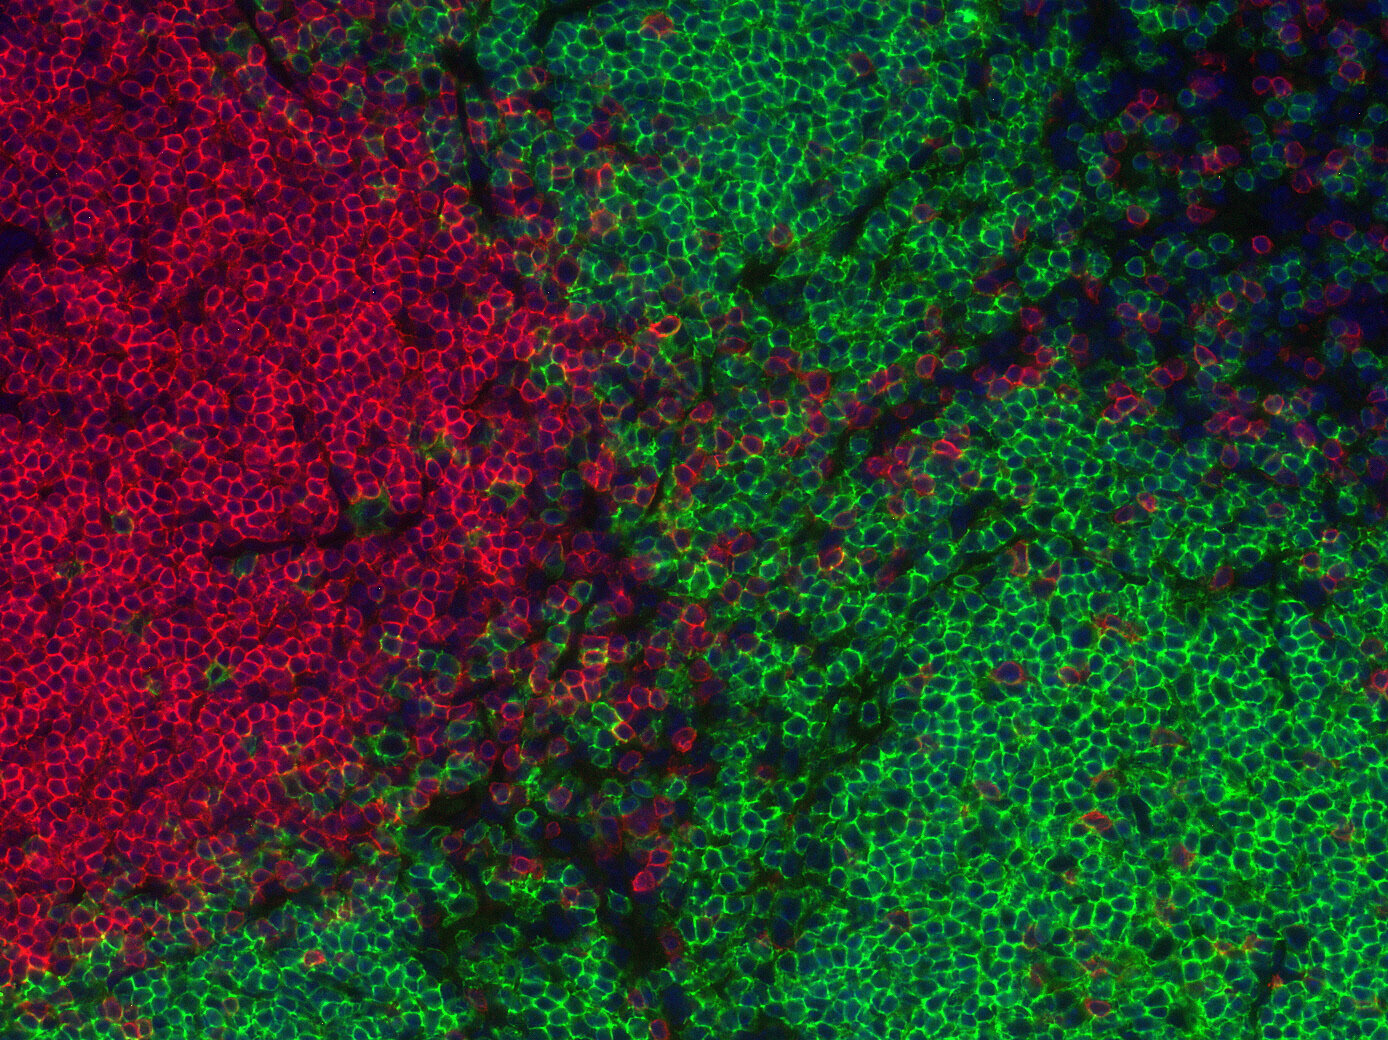

Indirect immunostaining of a formalin fixed paraffin-embedded mouse breast cancer model with rabbit anti-mouse CD19 (cat. no.: HS-439 003; DAB). Nuclei have been visualized by haematoxylin staining (blue).